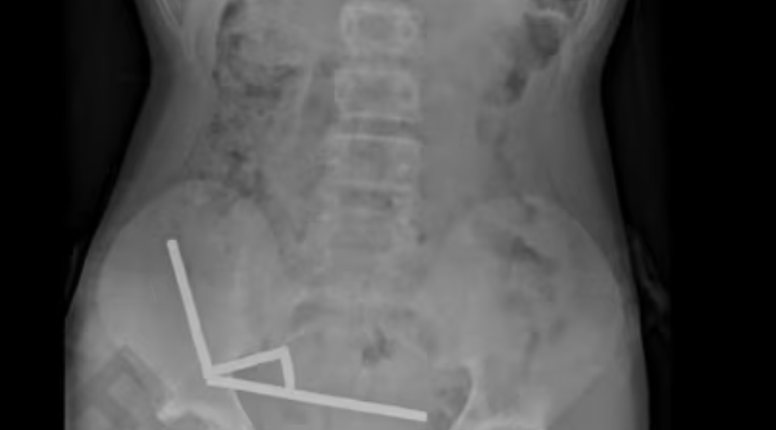

Rendgenska snimka abdomena otkrila je zastrašujući prizor - magneti su se unutar dječakovih crijeva grupirali u četiri kompaktne linije...

Rendgenska snimka abdomena otkrila je zastrašujući prizor – magneti su se unutar dječakovih crijeva grupirali u četiri kompaktne linije.

"Činilo se da se nalaze u odvojenim dijelovima crijeva koji su se slijepili zbog snažne magnetske sile", pojasnili su liječnici. Taj pritisak uzrokovao je nekrozu, odnosno odumiranje tkiva, na četiri mjesta u njegovom tankom i slijepom crijevu.